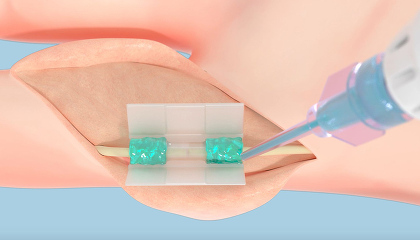

При проведении процедуры используется запатентованная система катетера, которая надежно захватывает и удаляет определенный фрагмент ткани из межпредсердной перегородки. Это приводит к шунтированию предсердий слева направо, что снижает повышенное давление в левом предсердии.